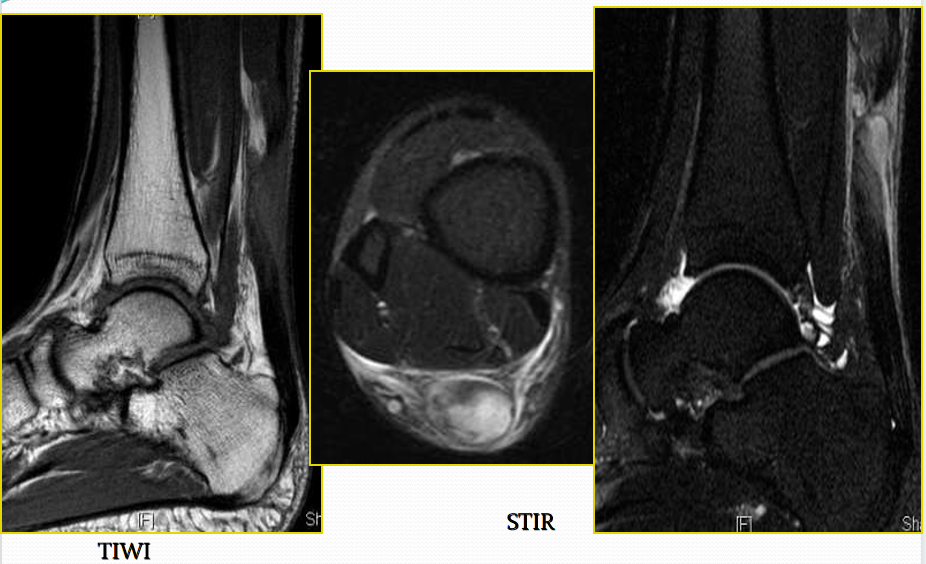

跟腱断裂

病因病理机制:

• 有体育运动史,对抗收缩力的足被动背屈(小腿三头肌群)

• 常位于跟骨上方2~6cm处发生断裂

• 类风湿性关节炎、系统性红斑狼疮、糖尿病和痛风

• 急性断裂:易患因素包括慢性跟腱炎和部分撕裂

MR表现:(信号+形态)

• 正常跟腱呈均匀低信号

• 脂肪抑制T2WI图像上,跟腱内部或跟腱周围软组织出血或水肿表现为信号增高,跟腱断裂/撕裂表现为跟腱连续性中断或波浪状回缩

• 跟腱近端回缩,跟腱边缘磨损,呈螺旋状形态

• 撕裂处增粗的近端与远端之间可见疏松的连接